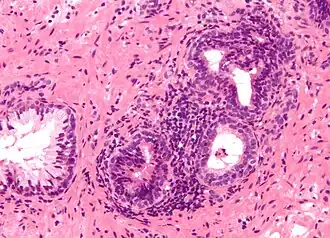

![]() Micrografía mostrando una glándula prostática inflamada, el correlato histológico de la prostatitis. A la izquierda de la imagen se observa una glándula normal no inflamada. Tinción hematoxilina-eosina. | ||